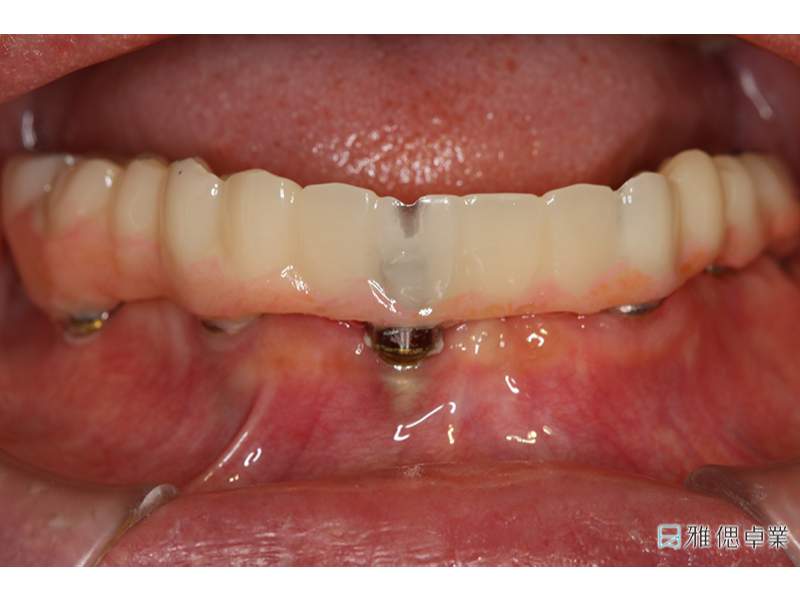

當日即可完成All on 6臨時假牙

All on 6植牙當天可立即裝戴臨時假牙